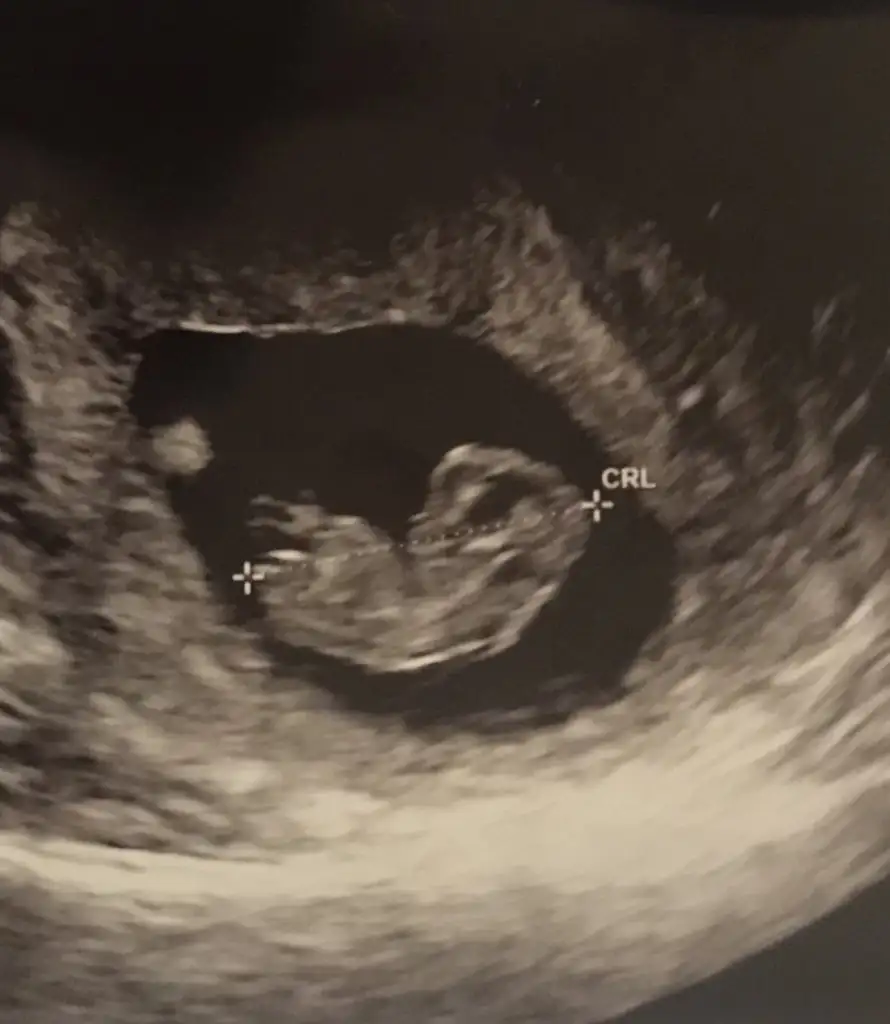

Teyzelerine el salladı size![]()